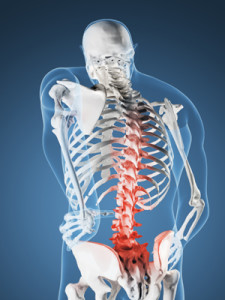

У многих больных наблюдается поражение костей именно в области позвоночника. Впрочем, иногда наблюдаются поражения и в костях черепа, а также таза. Симптомы болезни Педжета – сильная боль, деформация костей. Чаще всего, остеит возникает из-за переломов.

Обзор. Болезнь Педжета (PAJ-its) нарушает нормальный процесс регенерации костей в организме, при котором новая костная ткань постепенно заменяет старую. Со временем кости могут стать хрупкими и деформироваться. Чаще всего поражаются таз, череп, позвоночник и ноги.